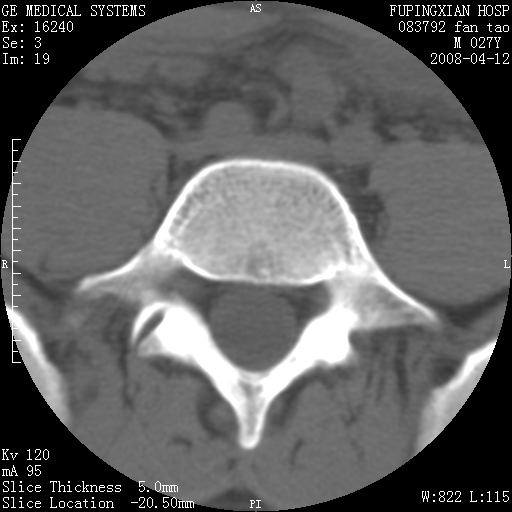

以下是引用前行在2008-4-13 13:53:00的发言:[br]椎间盘髓核终板下突出形成许莫氏结节及椎间盘突出,建议mr检查

以下是引用xclzq_910在2008-4-13 12:43:00的发言:[br]这个应该没什么了,椎间盘突出后反应性骨质吸收硬化.建议mr